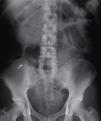

Paciente masculino de 66 años de edad, sin antecedentes de importancia, que ingresó al hospital con cuadro clínico de dolor abdominal de 36 h de evolución compatible con apendicitis aguda. Los laboratorios a su ingreso revelaron: 21.500 leucocitos/cc, neutrófilos 84.8%; el resto, normal. La placa simple de abdomen anteroposterior reveló la presencia de 2 objetos metálicos radiopacos, filiformes, puntiformes, de aproximadamente 5cm, localizados en el cuadrante inferior derecho del abdomen (fig. 1). En el interrogatorio dirigido negó la ingesta de algún cuerpo extraño en los días o meses previos. Se estableció el diagnóstico de perforación intestinal secundaria a cuerpos extraños versus apendicitis secundaria a cuerpos extraños. Se realizó una laparotomía exploradora en la que se encontró un apéndice retrocecal de aproximadamente 9cm, con perforación en su tercio medio, por donde protruía la punta de un alfiler, con el resto del cuerpo y un segundo alfiler dentro de la luz apendicular. Se le realizó una apendicectomía sin eventualidades. Se corroboró en el quirófano, mediante radiografía de la pieza, la presencia de ambos cuerpos extraños dentro de la luz apendicular (fig. 2). El reporte histológico de la pieza fue de apendicitis aguda abscesada y la presencia de 2 alfileres en su lumen (fig. 3). El paciente evolucionó satisfactoriamente y se egresó por mejoría 48 h después de la cirugía.